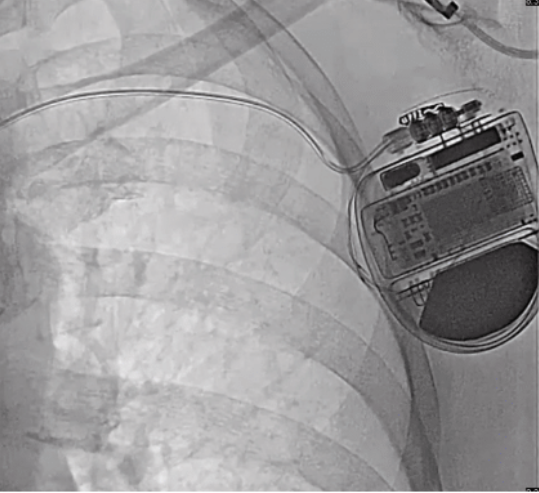

The patient is a 68-year-old woman with past medical history of nonischemic cardiomyopathy status post primary prevention single-chamber TV-ICD implantation in 2019. In September 2023, she presented to our office after noticing a beeping noise coming from her device. Remote transmission was concerned for right ventricular (RV) lead fracture with RV lead impedance greater than 3000 ohms. This was confirmed with a chest x-ray (CXR), which showed a fracture of the lead at the entry site of the axillary vein (Figure 1). After shared decision-making, she opted to proceed with extraction of the TV-ICD and implantation of an EV-ICD.

Device parameters at the time of implant were ring 1-ring 2 (608 ohms), ring 1-coil 2 (304 ohms), high voltage (HV) 75 ohms, and R-wave sensing 1.6 mV. Postoperative CXR (Figure 3) showed appropriate lead positioning. The patient remained stable with no complications throughout hospital admission and was discharged home the following day. During 3-month follow-up, her device interrogation showed stable lead parameters with R-wave sensing of 2.6 mV and few runs of nonsustained VT (1-4 seconds duration) due to oversensing.